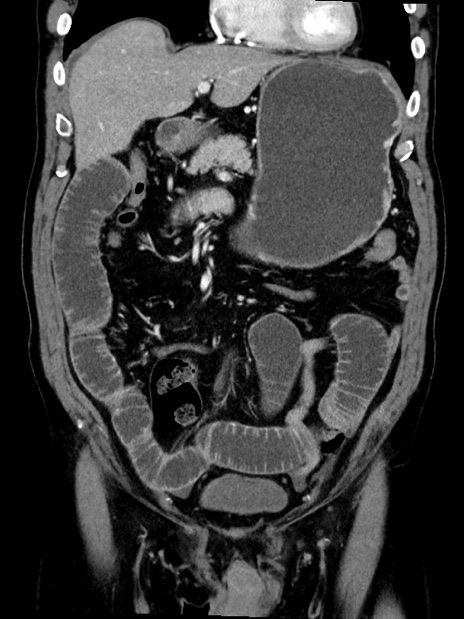

症例35(冠状断像)

【症例】70歳代 男性

【主訴】腹部膨満、嘔吐

【現病歴】昨日より腹部膨満感出現。本日増悪し、仙痛出現。嘔吐あり、受診。

【既往歴】糖尿病、胆摘後

【身体所見】BP 149/80mmHg、HR 74/min、BT 35.9℃、腹部:膨満、軟、圧痛なし。腸雑音減弱あり。上腹部正中切開瘢痕あり。

【データ】WBC 13500、CRP 1.72